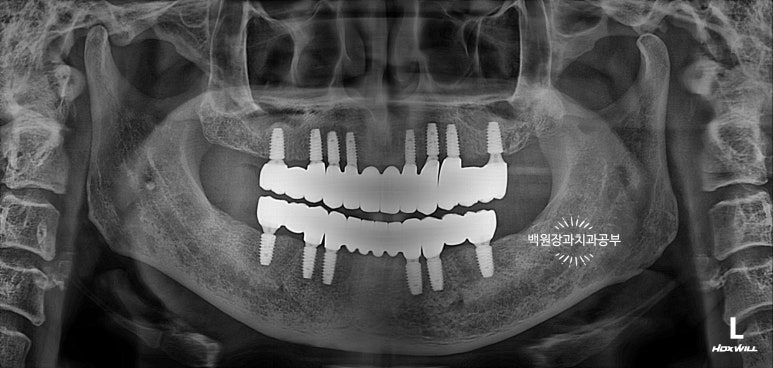

환자분의 구강 내에 맞춤형 지대주를 연결하고 임시치아를 붙여드렸습니다.

맞습니다! 환자분 입 안에 만들어온 맞춤형 지대주를 그대로 연결해드렸습니다.

아래가 기공소에서 받아왔던 상태이고, 위 사진이 받아온 맞춤형 지대주를 입 안에서 모두 연결한 상태입니다.

그리고 임시치아를 붙여드렸습니다.

사실 임시치아라 치아 모양도 둥글둥글하고 색깔도 예쁘지 않습니다.

그리고 임시 치아 사이에 간격도 존재하구요.

정면에서 보시면 임시 치아와 다르게 훨씬 깊이감 있는 색상으로 제작되어 자연스럽고, 완성도 있는 형태를 확인하실 수 있습니다.